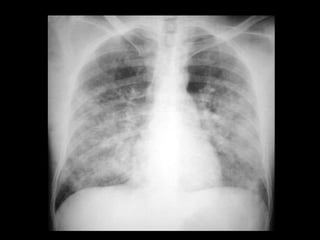

Infiltrado en alasde mariposa ó de murciélago, por edema pulmonar . Líneas B de Kerley .

Existe también cefalización de flujo. También llamado redistribución de flujo.